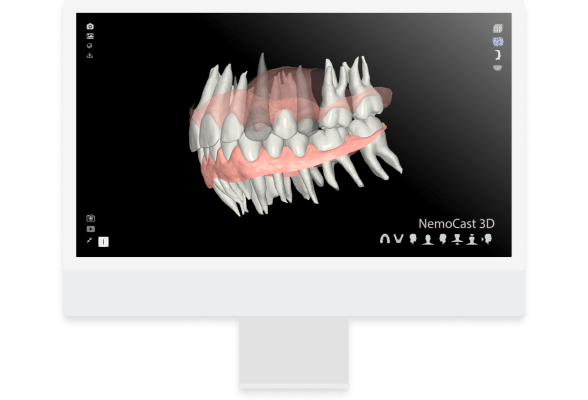

- Comprehensive Digital Workflow

Analyze and plan treatments seamlessly — from digital models and intraoral scans to the final appliance production stage. NemoCast ensures precision, efficiency, and full control throughout the digital workflow.

- AI‑Assisted Segmentation & Virtual Setup

Automatic tooth and crown segmentation, overlay visualizations, simulation of treatment progress.